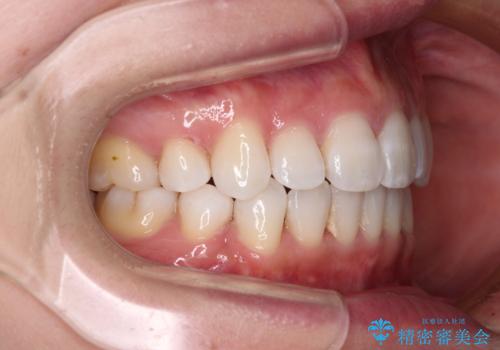

出っ歯を改善 目立たないワイヤー装置での抜歯矯正

2年~2年半が治療期間の目安でしたが、順調に治療が進み、1年9か月で満足のいく歯列となりました。